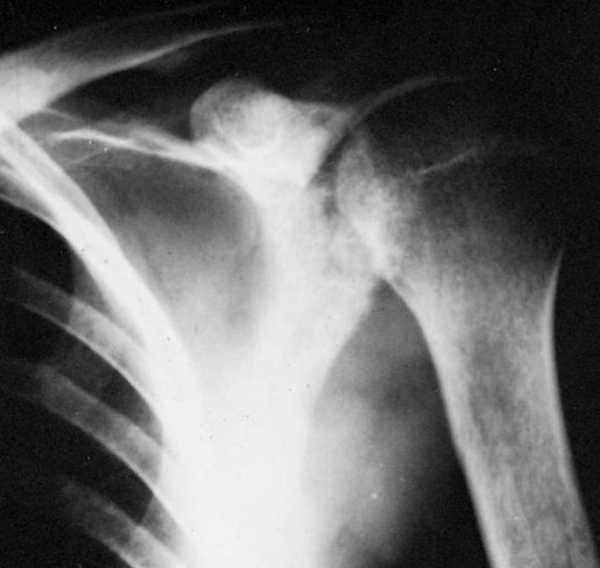

Рентген

С помощью рентгеновских лучей можно выявить наличие множества заболеваний, которые нельзя заметить невооруженным глазом. При этом такой диагностический метод не имеет болевых ощущений и доступен по своей стоимости. На сделанном снимке пораженные участки костей видны, как темноватые пятна, а ещё можно наблюдать увеличивающееся расстояние между суставами, а также их сращение. Внутри костей может быть видно истончение или полостные образования, ткани могут быть подвергнуты абсцессу, как правило это наблюдается вокруг больной кости.

Как диагностируется заболевание

Все пациенты при подозрении на костный туберкулез проходят рентгенографию или томографию пораженного органа в двух проекциях. При этом следует определить очаг костного разрушения (секвестры) и тени от абсцессов.

Признаки болезни можно увидеть на рентгеновских снимках. Между суставами появляются расстояния, изменяется костная структура, поверхность хрящей становится неровной, в кости появляются полости. Пораженные суставы можно определить по наличию припухлостей тканей или их атрофии.

Рентгеновские лучи уже много лет позволяют диагностировать много болезней, которые не видимы для глаза. Метод диагностики не сопровождается болевыми ощущениями и является доступным.

На рентгеновском снимке пораженные костные участки видны как темные пятна. Можно увидеть изменение расстояния между суставами или их сращение.

Выявляется истончение или образование внутрикостных полостей, наличие абсцессов в тканях, вокруг пораженной кости.

Костный туберкулез в первую очередь диагностируется рентгенологически. Хотя в начальных стадиях болезни на рентгеновских снимках разрушения кости еще не видно — на рентгене видны разрушения, когда потеряно более 50% костной ткани. А вот на компьютерных томографах, чья чувствительность выше, можно обнаружить деструктивные изменения кости в начальной стадии.